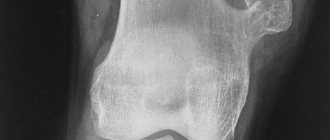

При рентгенологической диагностике болезни Осгуда-Шлаттера необходимо иметь в виду множество вариантов нормальной оссификации апофиза большеберцовой кости. Чаще всего апофиз окостеневает в виде хоботообразного отростка в возрасте 10-13 лет, но встречаются варианты с добавочными мелкими ядрами окостенения. Слияние апофиза с метафизом происходит к 16-18 годам.

При диагностике всегда следует учитывать несоответствие между значительным выбуханием бугристости при клиническом исследовании и почти нормальными размерами апофиза на рентгенограмме. Предпочтение необходимо отдавать клиническим данным.